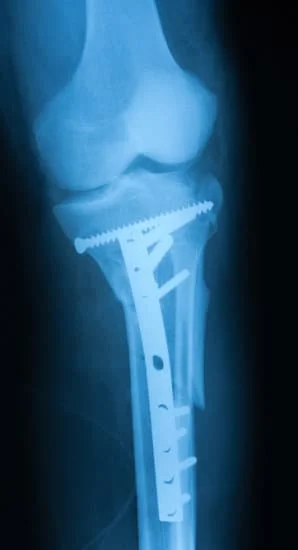

Quality and affordable healthcare has long been the essence in the field of medical sciences & treatment. Every patient expects an early diagnosis and a planned approach to treatment procedures with affordability and access to quality healthcare. Knee replacement, Hip replacement, Fracture treatment are being done by Dr.P.Sankaralingam at very affordable costs without compromising on quality.

Dr.P.Sankaralingam M.S(ortho)., DNB (ortho).,MNAMS is an experienced senior consultant Orthopaedic surgeon who does about 350 joint replacement surgeries per year in addition to treatment of Trauma cases.

• All Trauma & Fracture Fixation (Nails, Plates, Non-union Repairs)

Accomplishment